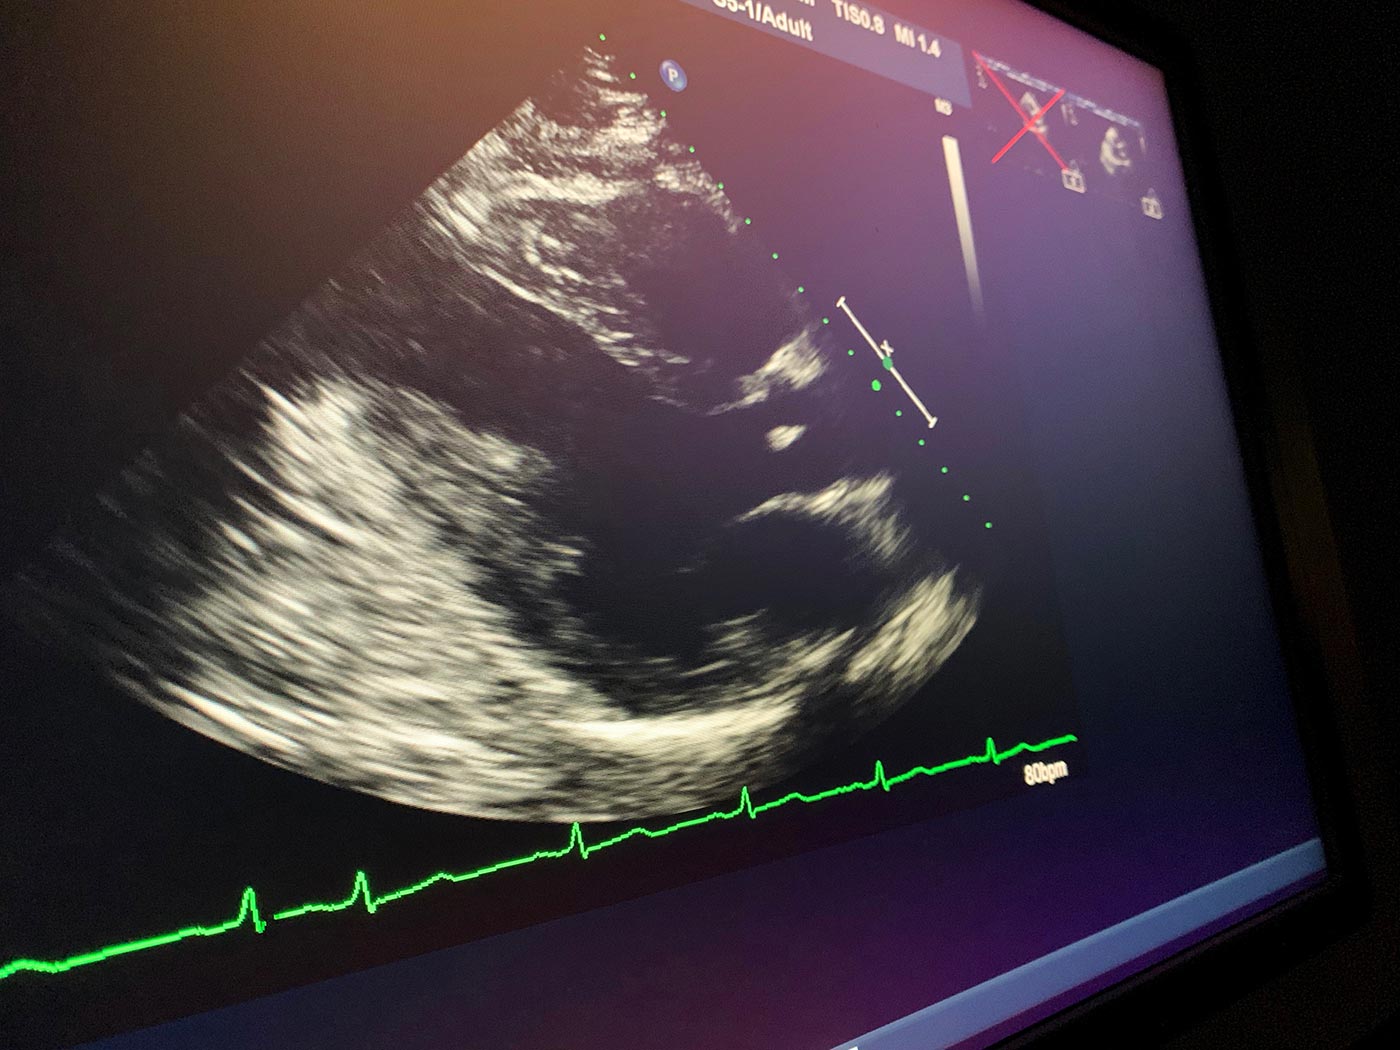

September 4, 2019 - Wednesday - I had my follow up cardiograph today. My doctor gave me the good news that my heart function is back to normal. Even better I don't have to wear the defibrillator vest anymore. I think that might be the best news. Wearing that thing sucked!